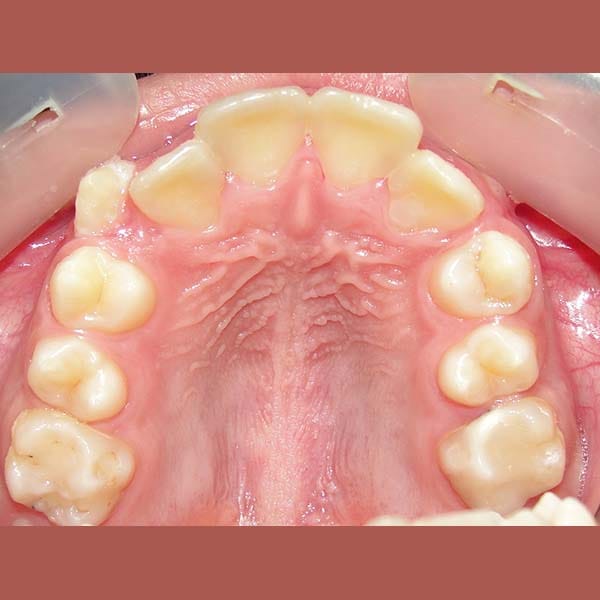

BEFORE